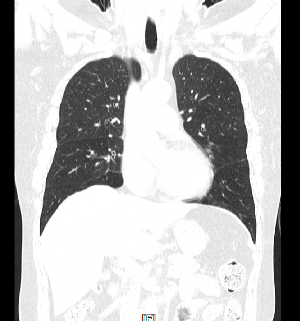

의료용 방사선을 이용하는 X-ray 검사와 비교할 때 인체의 해부학적 구조물이 겹쳐져 보이지 않고 인체의 축상면을 영상으로 획득합니다.

획득된 영상을 전산화된 프로그램을 이용하여 3차원(3D) 영상으로 재구성이 용이하며 인체의 시상면, 관상면 재구성도 가능합니다.